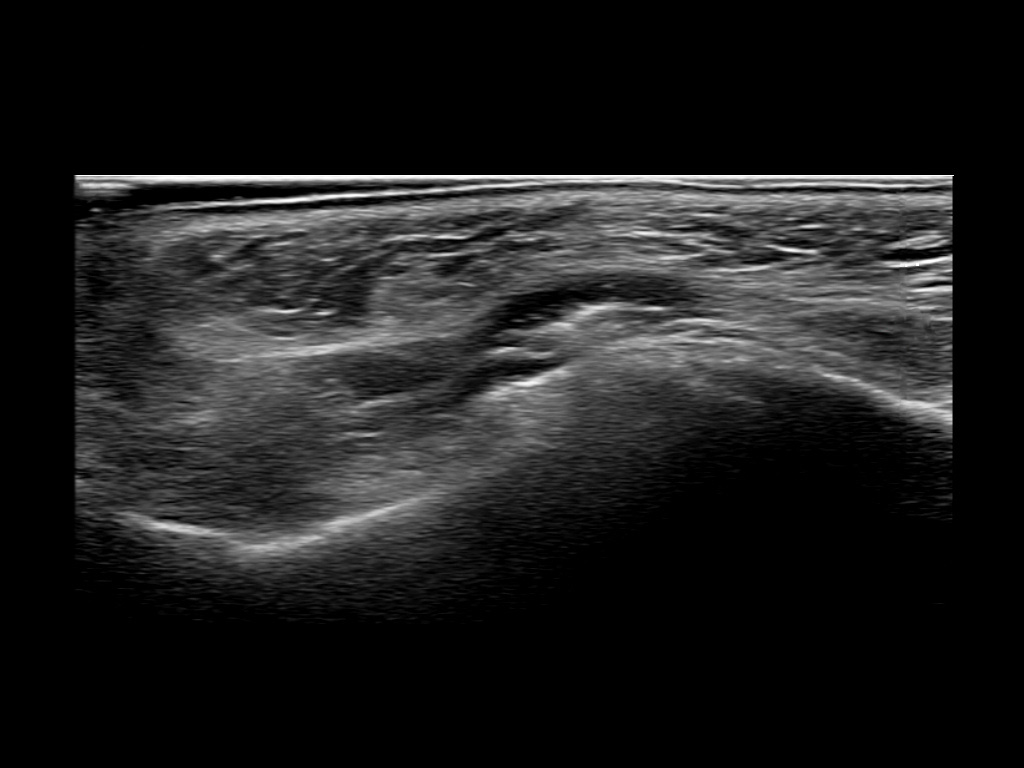

Study the first image to recognize the different layers. If you are sure about the layers, swipe to the second image to view the answer (if applicable).